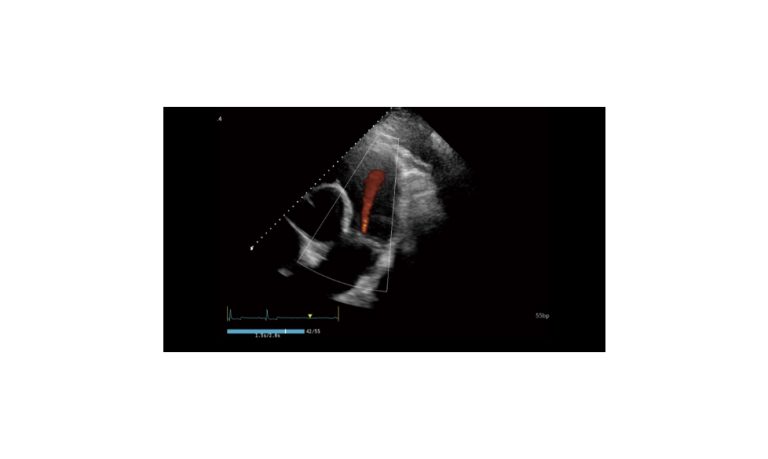

SonoScape Pro Pet E11

Smart Imaging

Introducing the first portable ultrasound with the C-Field+TM platform, redefining diagnostic imaging. Designed for veterinarians, it delivers unmatched clarity, ultra-fast processing, and seamless adaptability for all species. Experience Smart Imaging, Heartfelt Care—anywhere.

Equipped with cutting-edge veterinary software and optimized workflows, it embodies our commitment to Smart Imaging, Heartfelt Care – Wherever Their Journey Leads, with unparalleled performance and adaptability, this innovative system empowers veterinarians to provide exceptional care across all diagnostic applications,